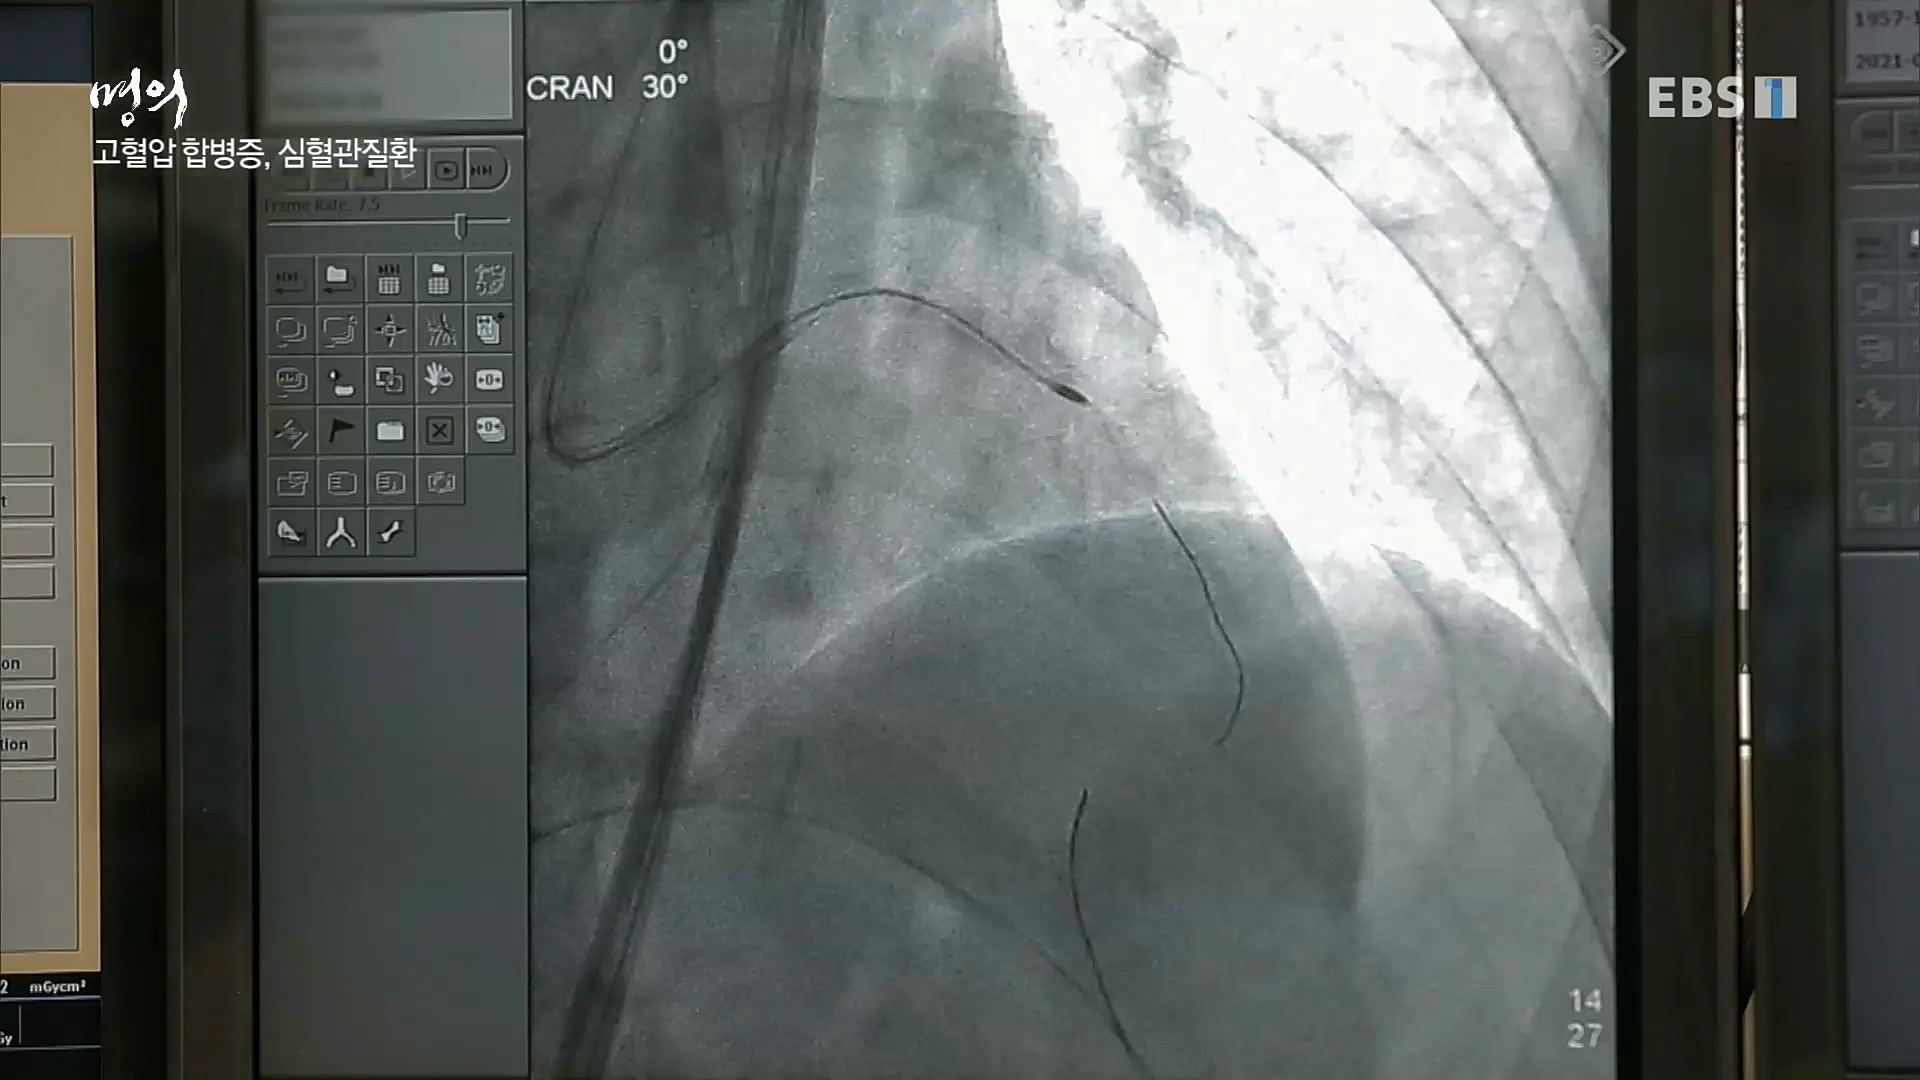

[한국강사신문 정헌희 기자] 오늘 12일(금) 21시 50 EBS1 <명의>에서는 강북삼성병원 순환기내과 성기철 교수의 “아이고, 혈압이야 – 고혈압을 잡자!” ...

이날 고혈압 질환은 순환기내과 전문의 김철호 교수, 권현철 교수, 성기철 교수, 고지혈 질환은 심장내과 전문의 한기훈 교수, 혈관외과 전문의 ...